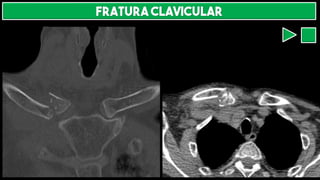

FRATURA CLAVICULAR